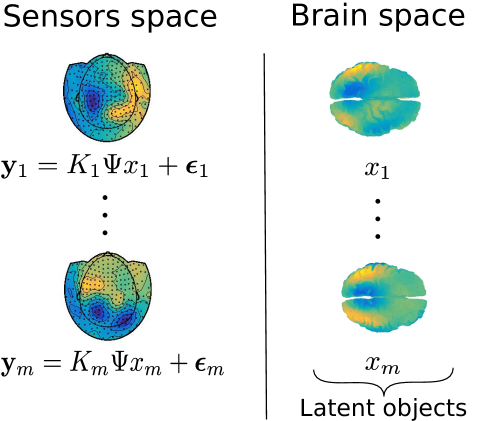

We consider the problem of estimating the PC functions in (5), and associated scores , from the observations . In Figure 3 we give an illustration of the introduced setting. Note that it would not be necessary to define the evaluation operator if the forward operators were defined to be functionals , relating directly the functional objects on the brain space to the real vectors on the sensors space. It is however the case that the operators are computed in a matrix form by third party software (see Section 6 for details) for a pre-specified set of points and it is thus convenient to take this into account in the model through the introduction of an evaluation operator .

where , and are the sampling points associated with the operator . The forward operators act on both sides of the covariance functions , due to the linear transformation applied to the signals on the brain space before being detected on the sensors space. The term is an error term, where is a matrix such that each entry is an independent sample of a Gaussian distribution with mean zero and standard deviation . Model (6) could be regarded as an implementation of the idealized Problem 2, where the covariance operators are represented by the associated covariance functions. An illustration of the setting introduced can be found in Figure 4.